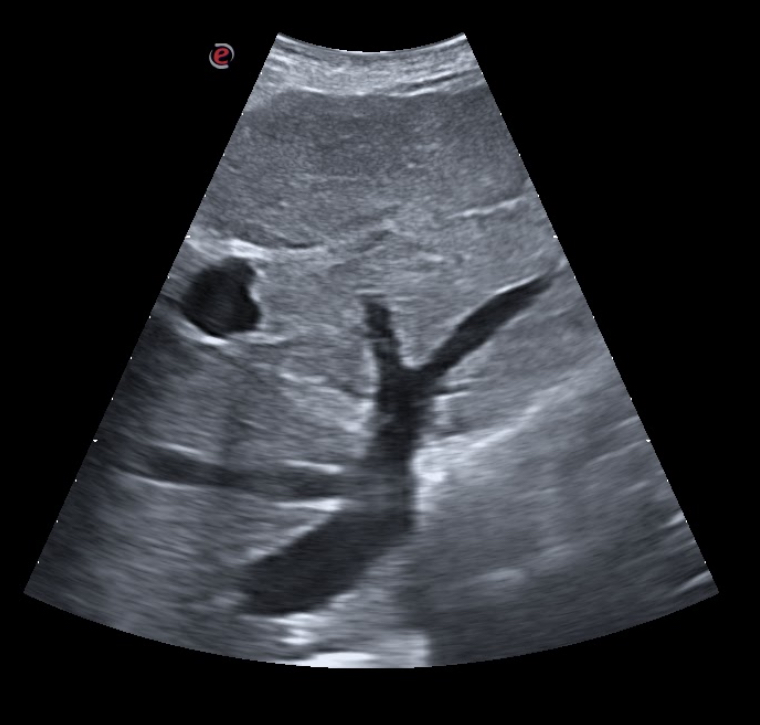

Se decidió realizar ecografía clínica pulmonar apreciándose líneas B en campos 2-4-6 de ambos pulmones con derrame en ambos senos costofrénicos visualizándose la cola de sirena y vena cava congestiva. La ecocardiografía realizada por los cardiólogos no mostró defectos en la contractilidad.